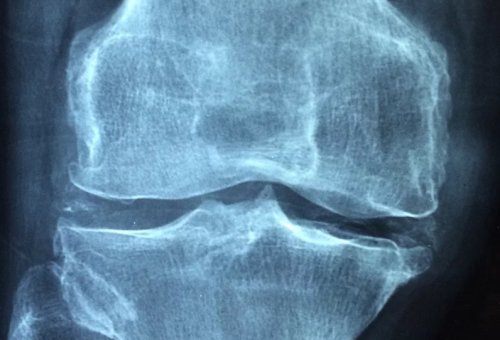

文章插图